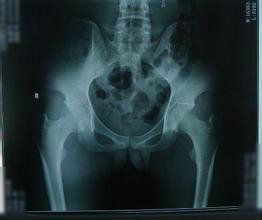

X线检查:关节附近有斑片状骨质疏松区,骨侵蚀和软骨下骨质硬化,骨骼变化明显。

CT显示:髂骨关节面模糊、局灶性骨质疏松、软骨下骨质轻度的侵蚀糜烂但关节间隙韧带正常。

(图:腰椎关节处有斑片状骨质疏松区)